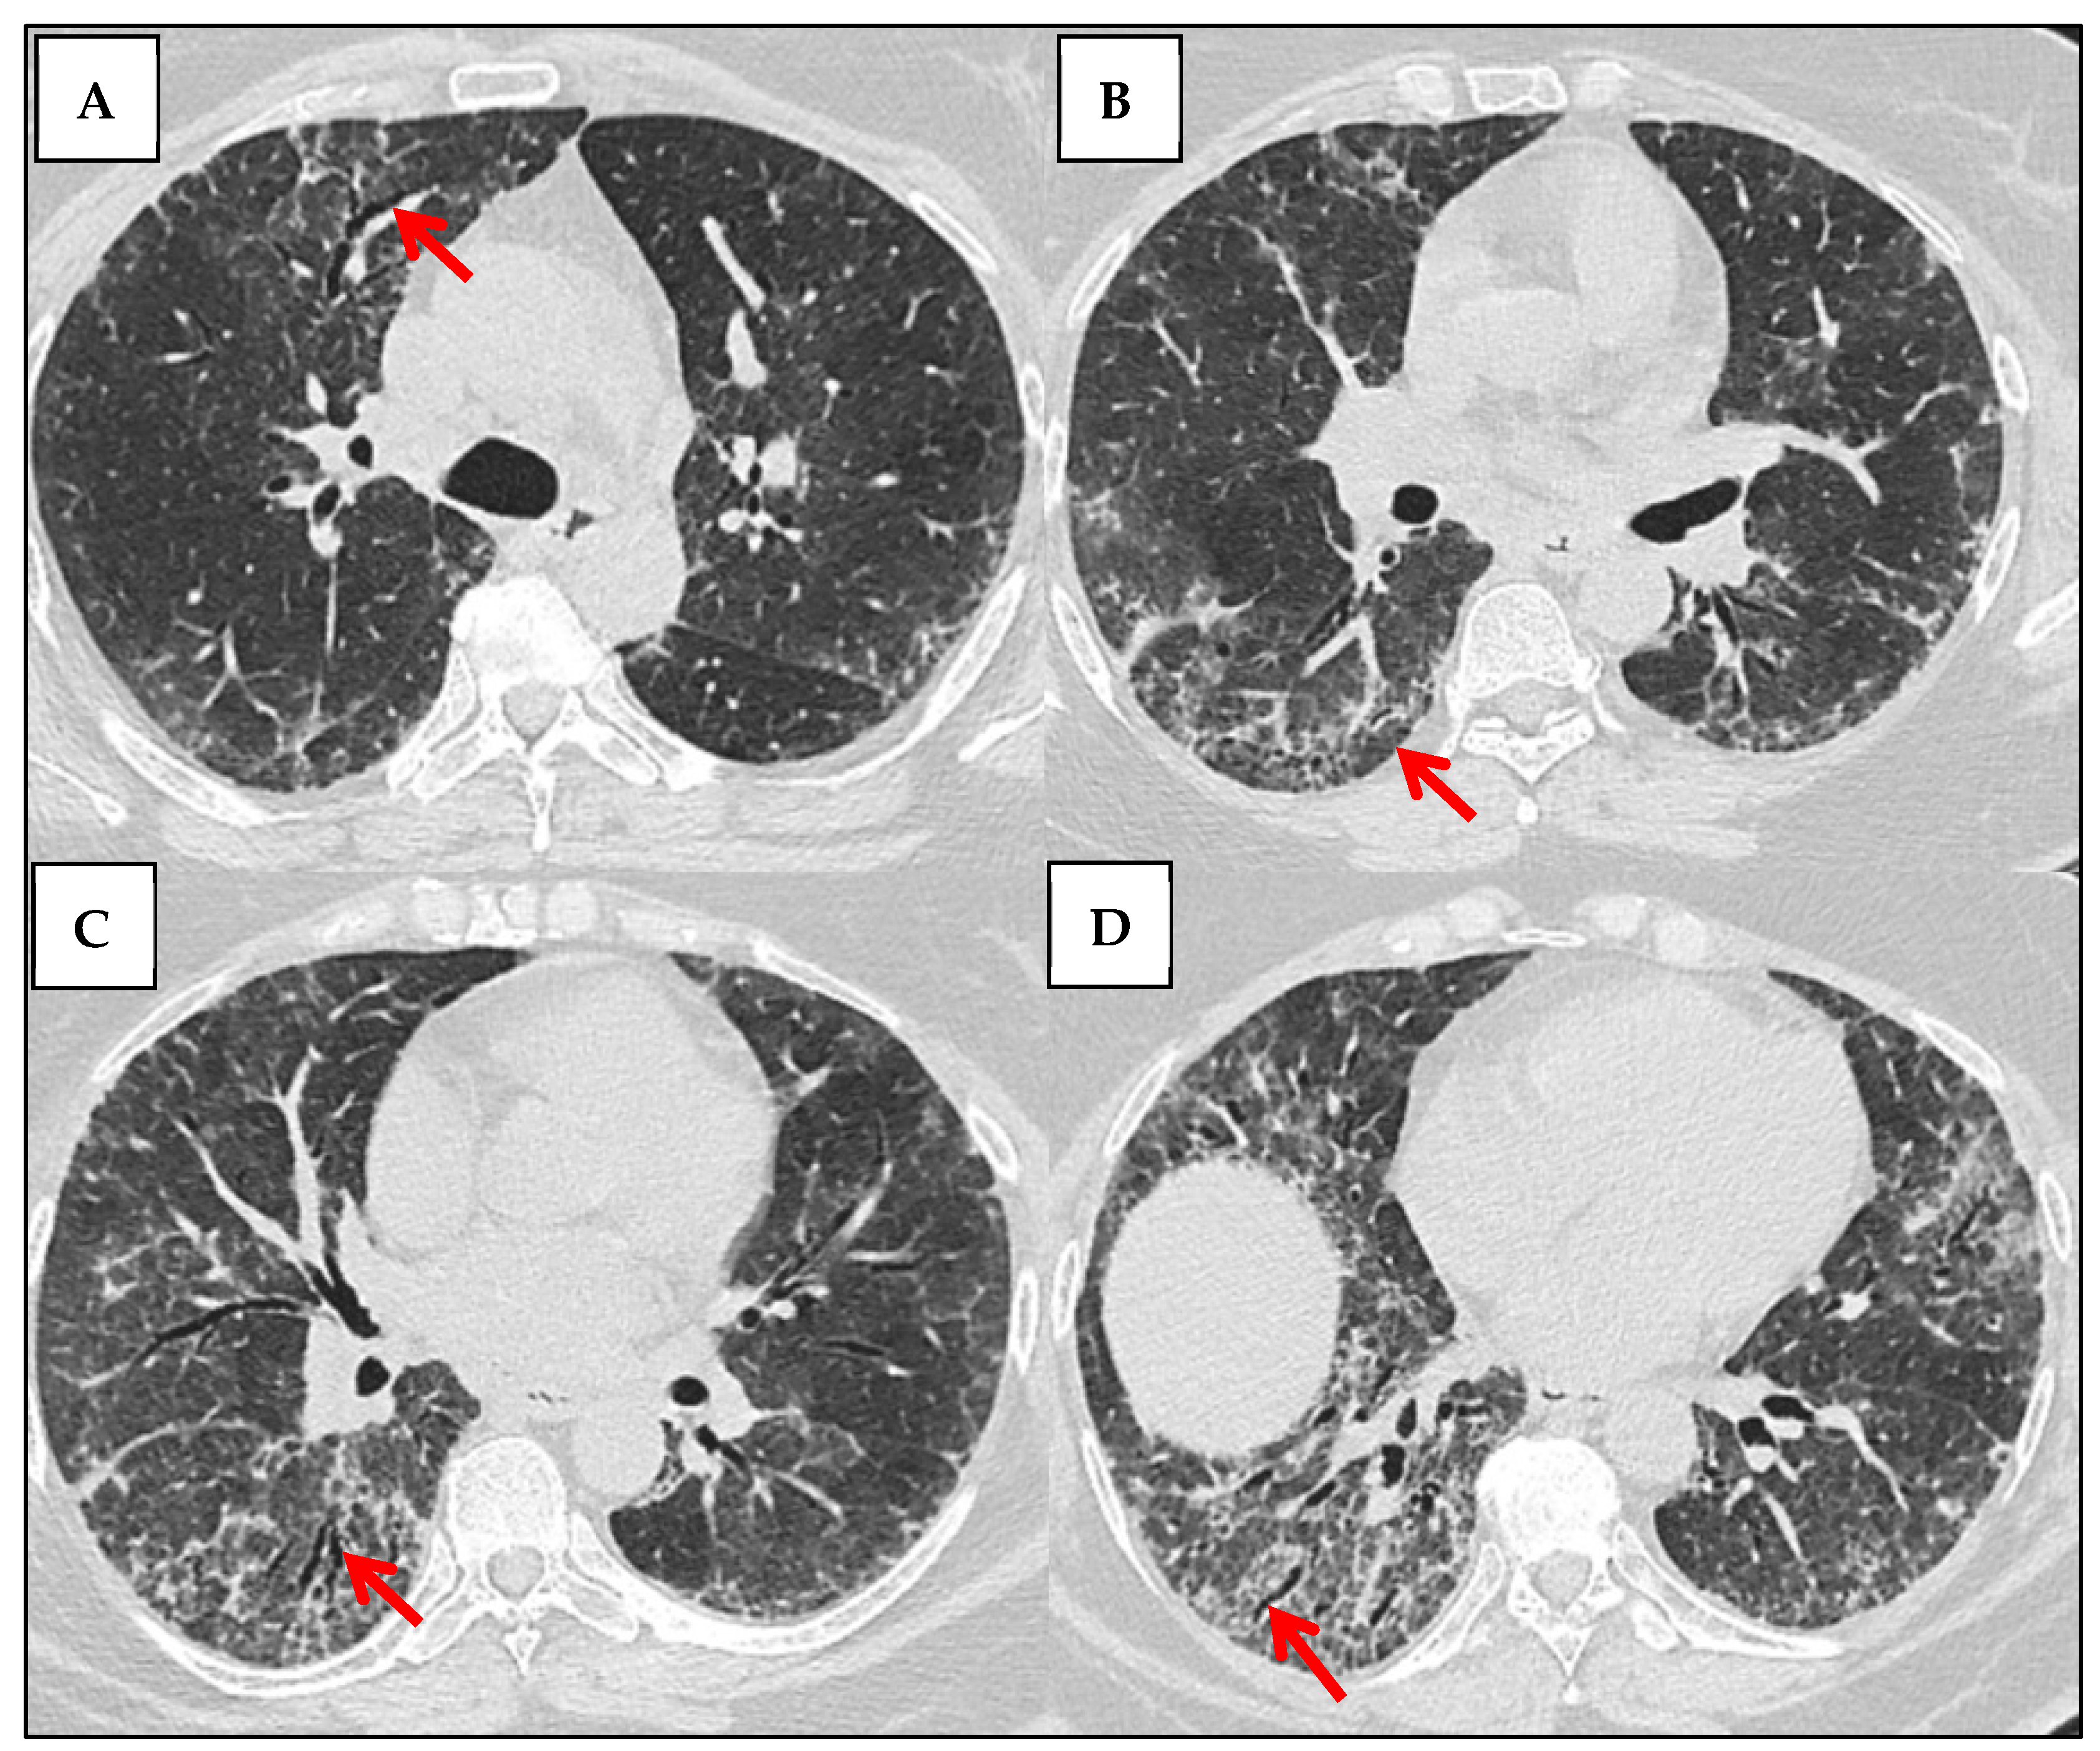

| Distinctive HRCT Signs | - Anterior upper lobe (AUL) sign  - Straight-edge (SE) sign - Exuberant honeycombing (EHC)  | [45] |

3.3.1. UIP Pattern

3.3.2. NSIP Pattern

3.3.3. OP Pattern

3.3.4. LIP Pattern